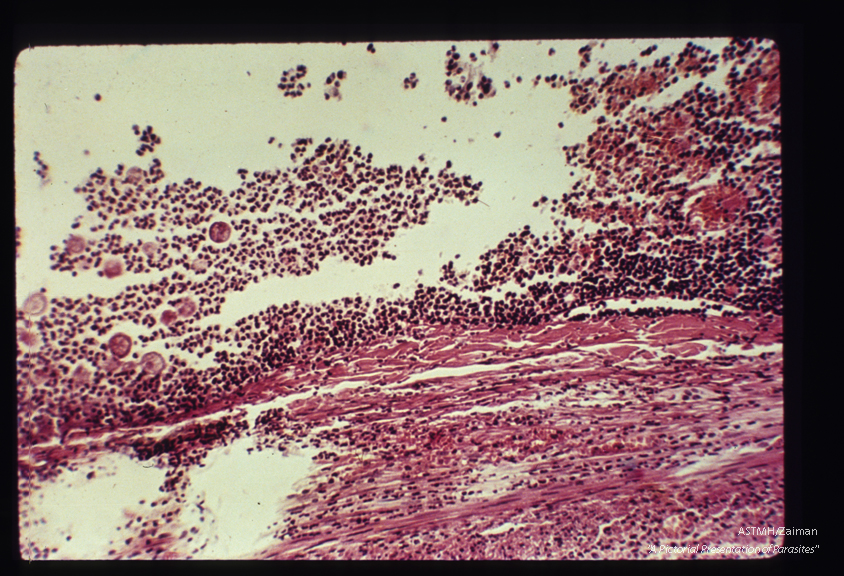

In human appendix; low and high power views of a highly inflamed appendix contain­ing trophozoites . H&E.

Entamoeba histolytica

Description: In human appendix; low and high power views of a highly inflamed appendix contain­ing trophozoites . H&E.